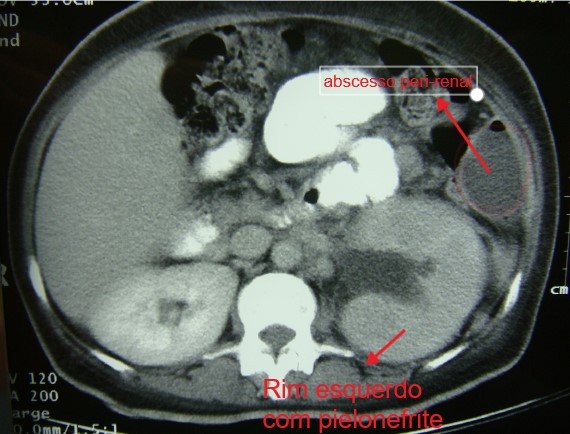

Abscesso Renal e Peri-Renal

A TC constitui o método preferencial para diagnosticar abscesso renal, caracterizando a extensão da infecção e auxiliando na identificação de sua origem. Embora o US também seja útil, pode não distinguir uma massa inflamatória de um abscesso renal verdadeiro.

O manejo inclui o diagnóstico precoce, instituição da terapia antimicrobiana eficaz e drenagem, tanto para fins terapêuticos quanto diagnóstico. A cultura do fluido identifica o agente etiológico e orienta a escolha do antibiótico. Abscessos pequenos (1 a 3 cm de diâmetro) frequentemente respondem à terapia antimicrobiana sem drenagem.

Entretanto, para abscessos maiores que três centímetros a drenagem é geralmente necessária.